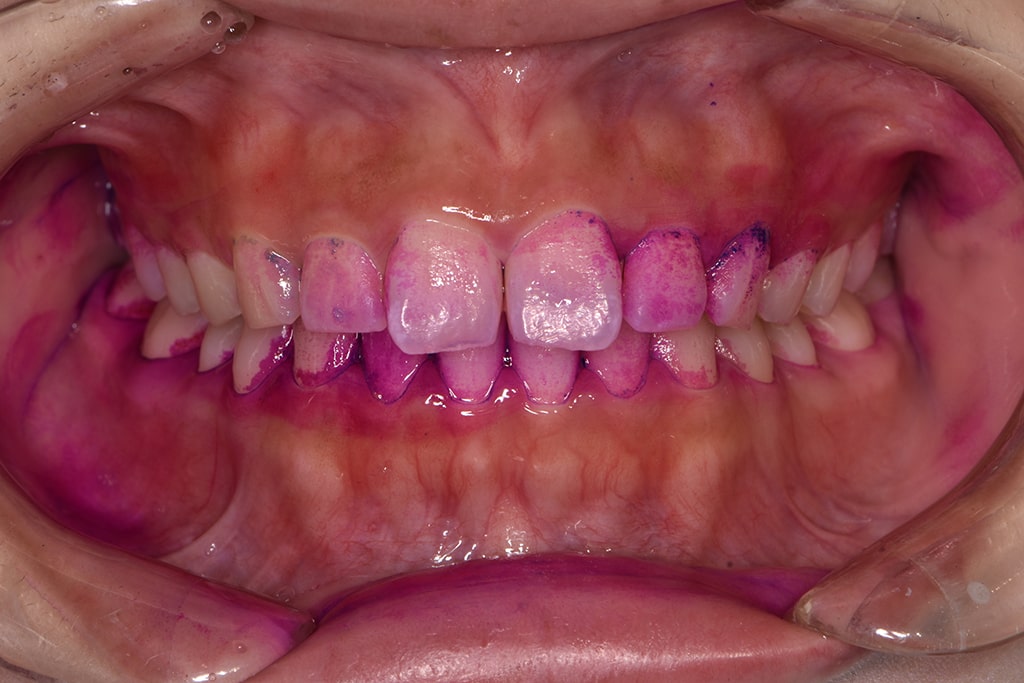

色素とプラーク内の酸の相互作用により、新しいプラークが赤く、古いものが青紫に、そしてう蝕リスクが高い場合は水色に染まります。この染め出しによって、患者様の口内の汚れが視覚的にわかりやすくなり、それが患者様のモチベーション向上に寄与します。

プラークの状態を可視化することで、治療や予防の努力が直接的な成果に結びつき、患者様のオーラルケアへのコミットメントが高まることが期待できます。

染め出しPCRとブラッシング指導

「染め出しPCR」とは、プラークに色をつけて付着具合を数値化することです。

さらに、染め出したプラークを効率的に除去するために、お一人お一人に適したブラッシング方法をお伝えいたします。